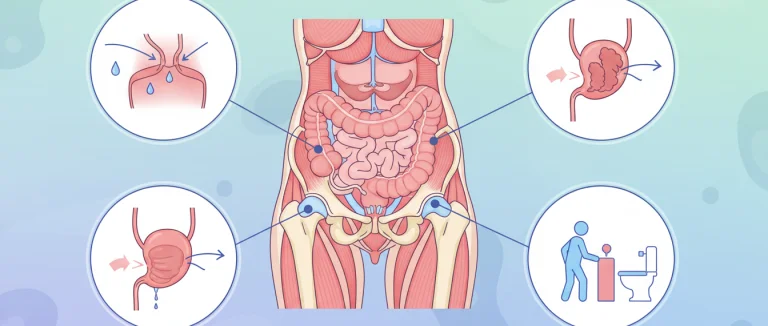

повышенное мочеиспускание

поддержка мочевого пузыря

подтекание мочи

постоянное желание мочиться

почему я так часто мочусь

препараты для контроля мочевого пузыря

протекание мочи

протекающий мочевой пузырь